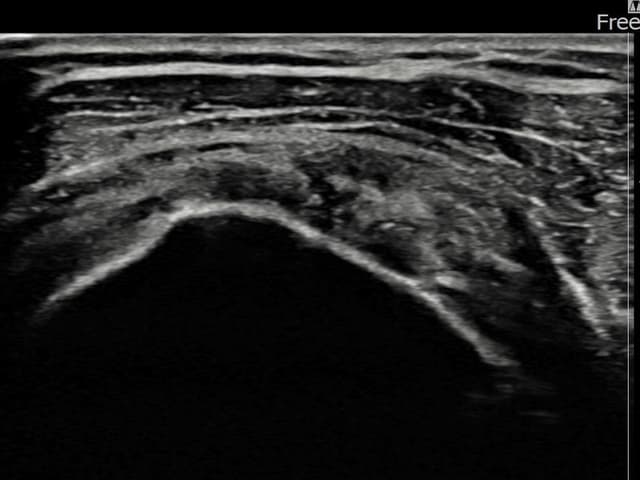

[経過期間: 24.01.08~24.03.14]

[縫縮術] 超音波検査にて左 棘上筋腱 関節面側部分断裂(3.5mm × 3.1mm (부분파열))を確認。縫縮術施行後、腱の連続性が回復し、日常生活に復帰されました。